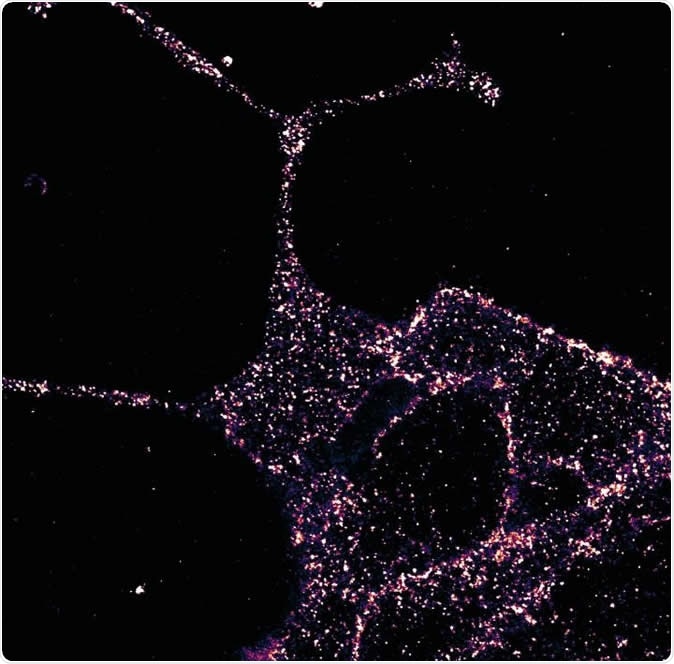

GLP1R visualized in insulin-secreting beta cells at super-resolution. Image Credit: University of Birmingham

They used several different methods of visualization, such as creating marker compounds in the form of fluorescent probes, immunostaining, super-resolution microscopy and the examination of the protein in live mice. Their probes were used to label the receptor which helped them locate it precisely inside the living mouse cell, as well as to understand how it responds to signaling chemicals. Super-resolution microscopy allows imaging at resolutions below the limit of wave diffraction. This makes it possible to study biological structures at resolutions comparable to the size of individual molecules. As a result, these are the preferred methods in visualizing proteins and the way they are organized within living cells.